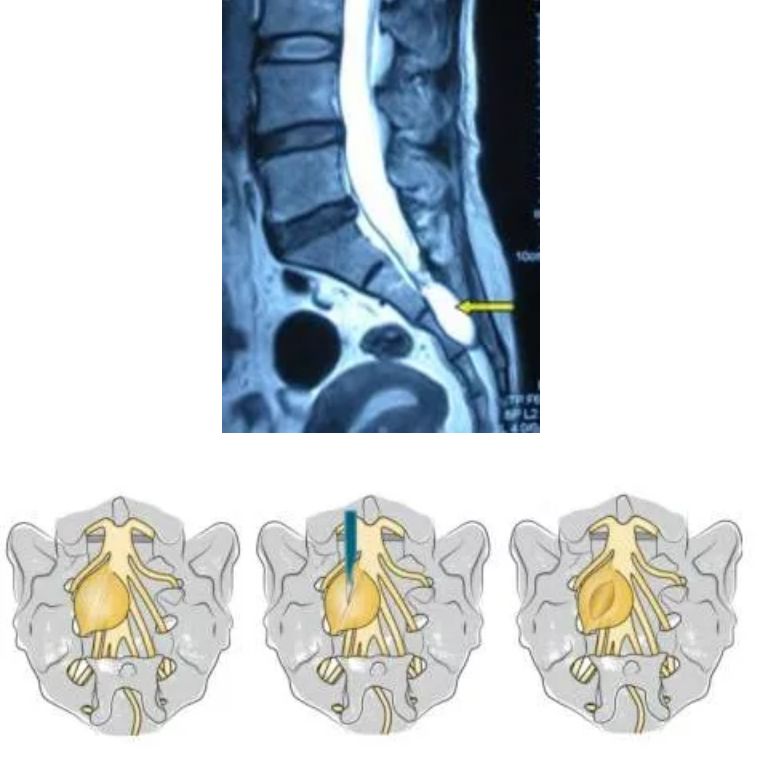

微创手术由于创伤小、恢复快等特点

是目前最佳的治疗方式。

经过沟通,娄永利为孟阿姨进行了微创骶管囊肿切除+终丝切断术+神经松解术。

术后孟阿姨就感觉肢体麻木减轻了许多,

目前,孟阿姨还在进一步康复中。